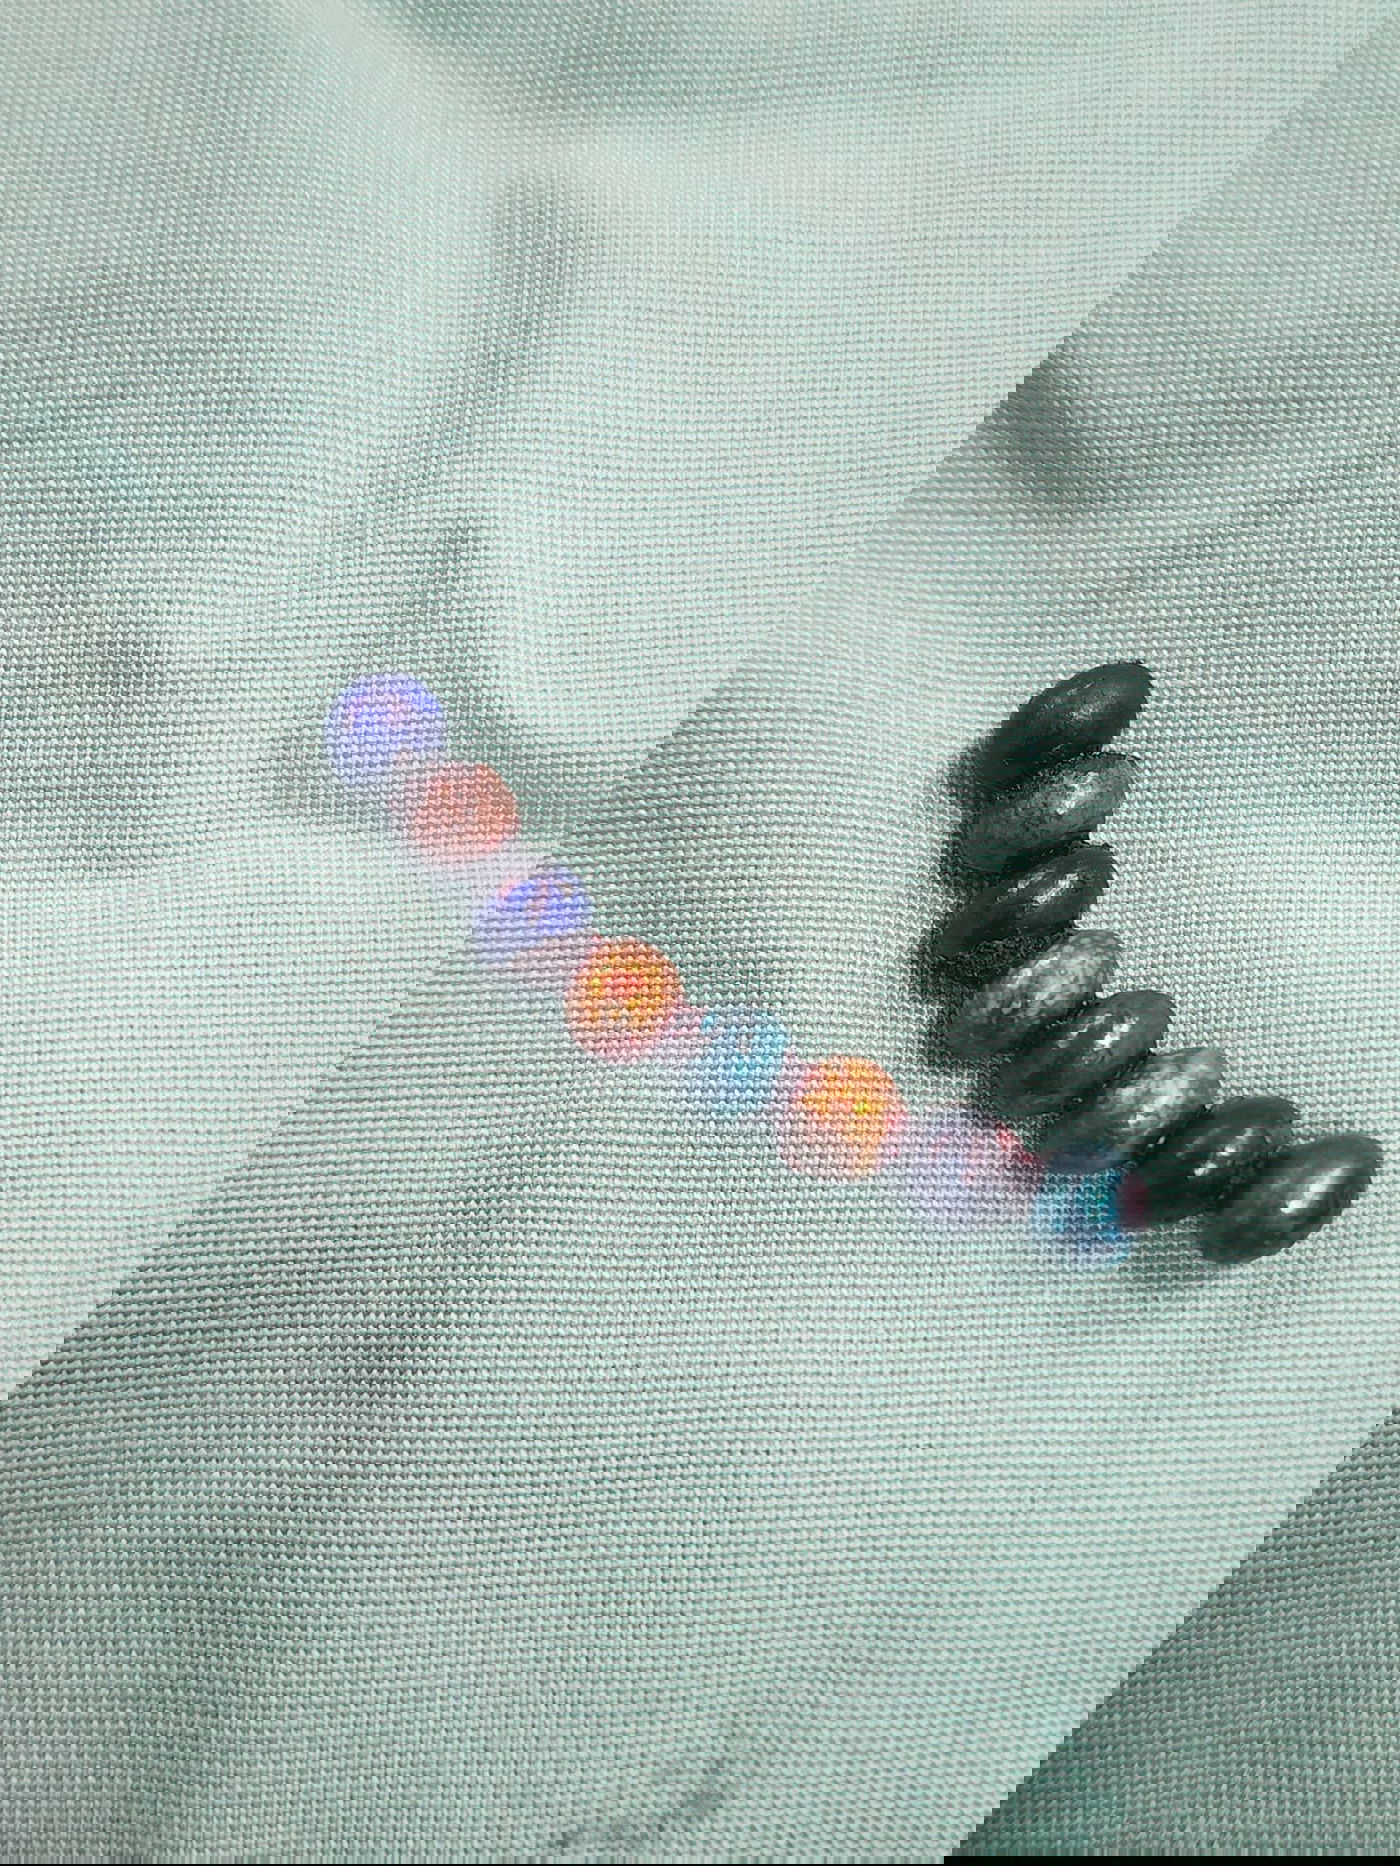

בהתייעצות עם ד"ר ראוף נאסר, מומחה גסטרו ילדים, הפעוט הופנה להמשך טיפול כירורגי ונותח באופן דחוף ע"י ד”ר דניאל דובין, סגן מנהלת מחלקת כירורגיית ילדים במרכז הרפואי בני ציון ו ד"ר יאיר בן שמואל, רופא בכיר בכירורגיית ילדים, כאשר ד"ר אבו ראס עומר היה הרופא המרדים הבכיר. בניתוח הוצאו שמונה כדורי מגנט מהמעי הדק.